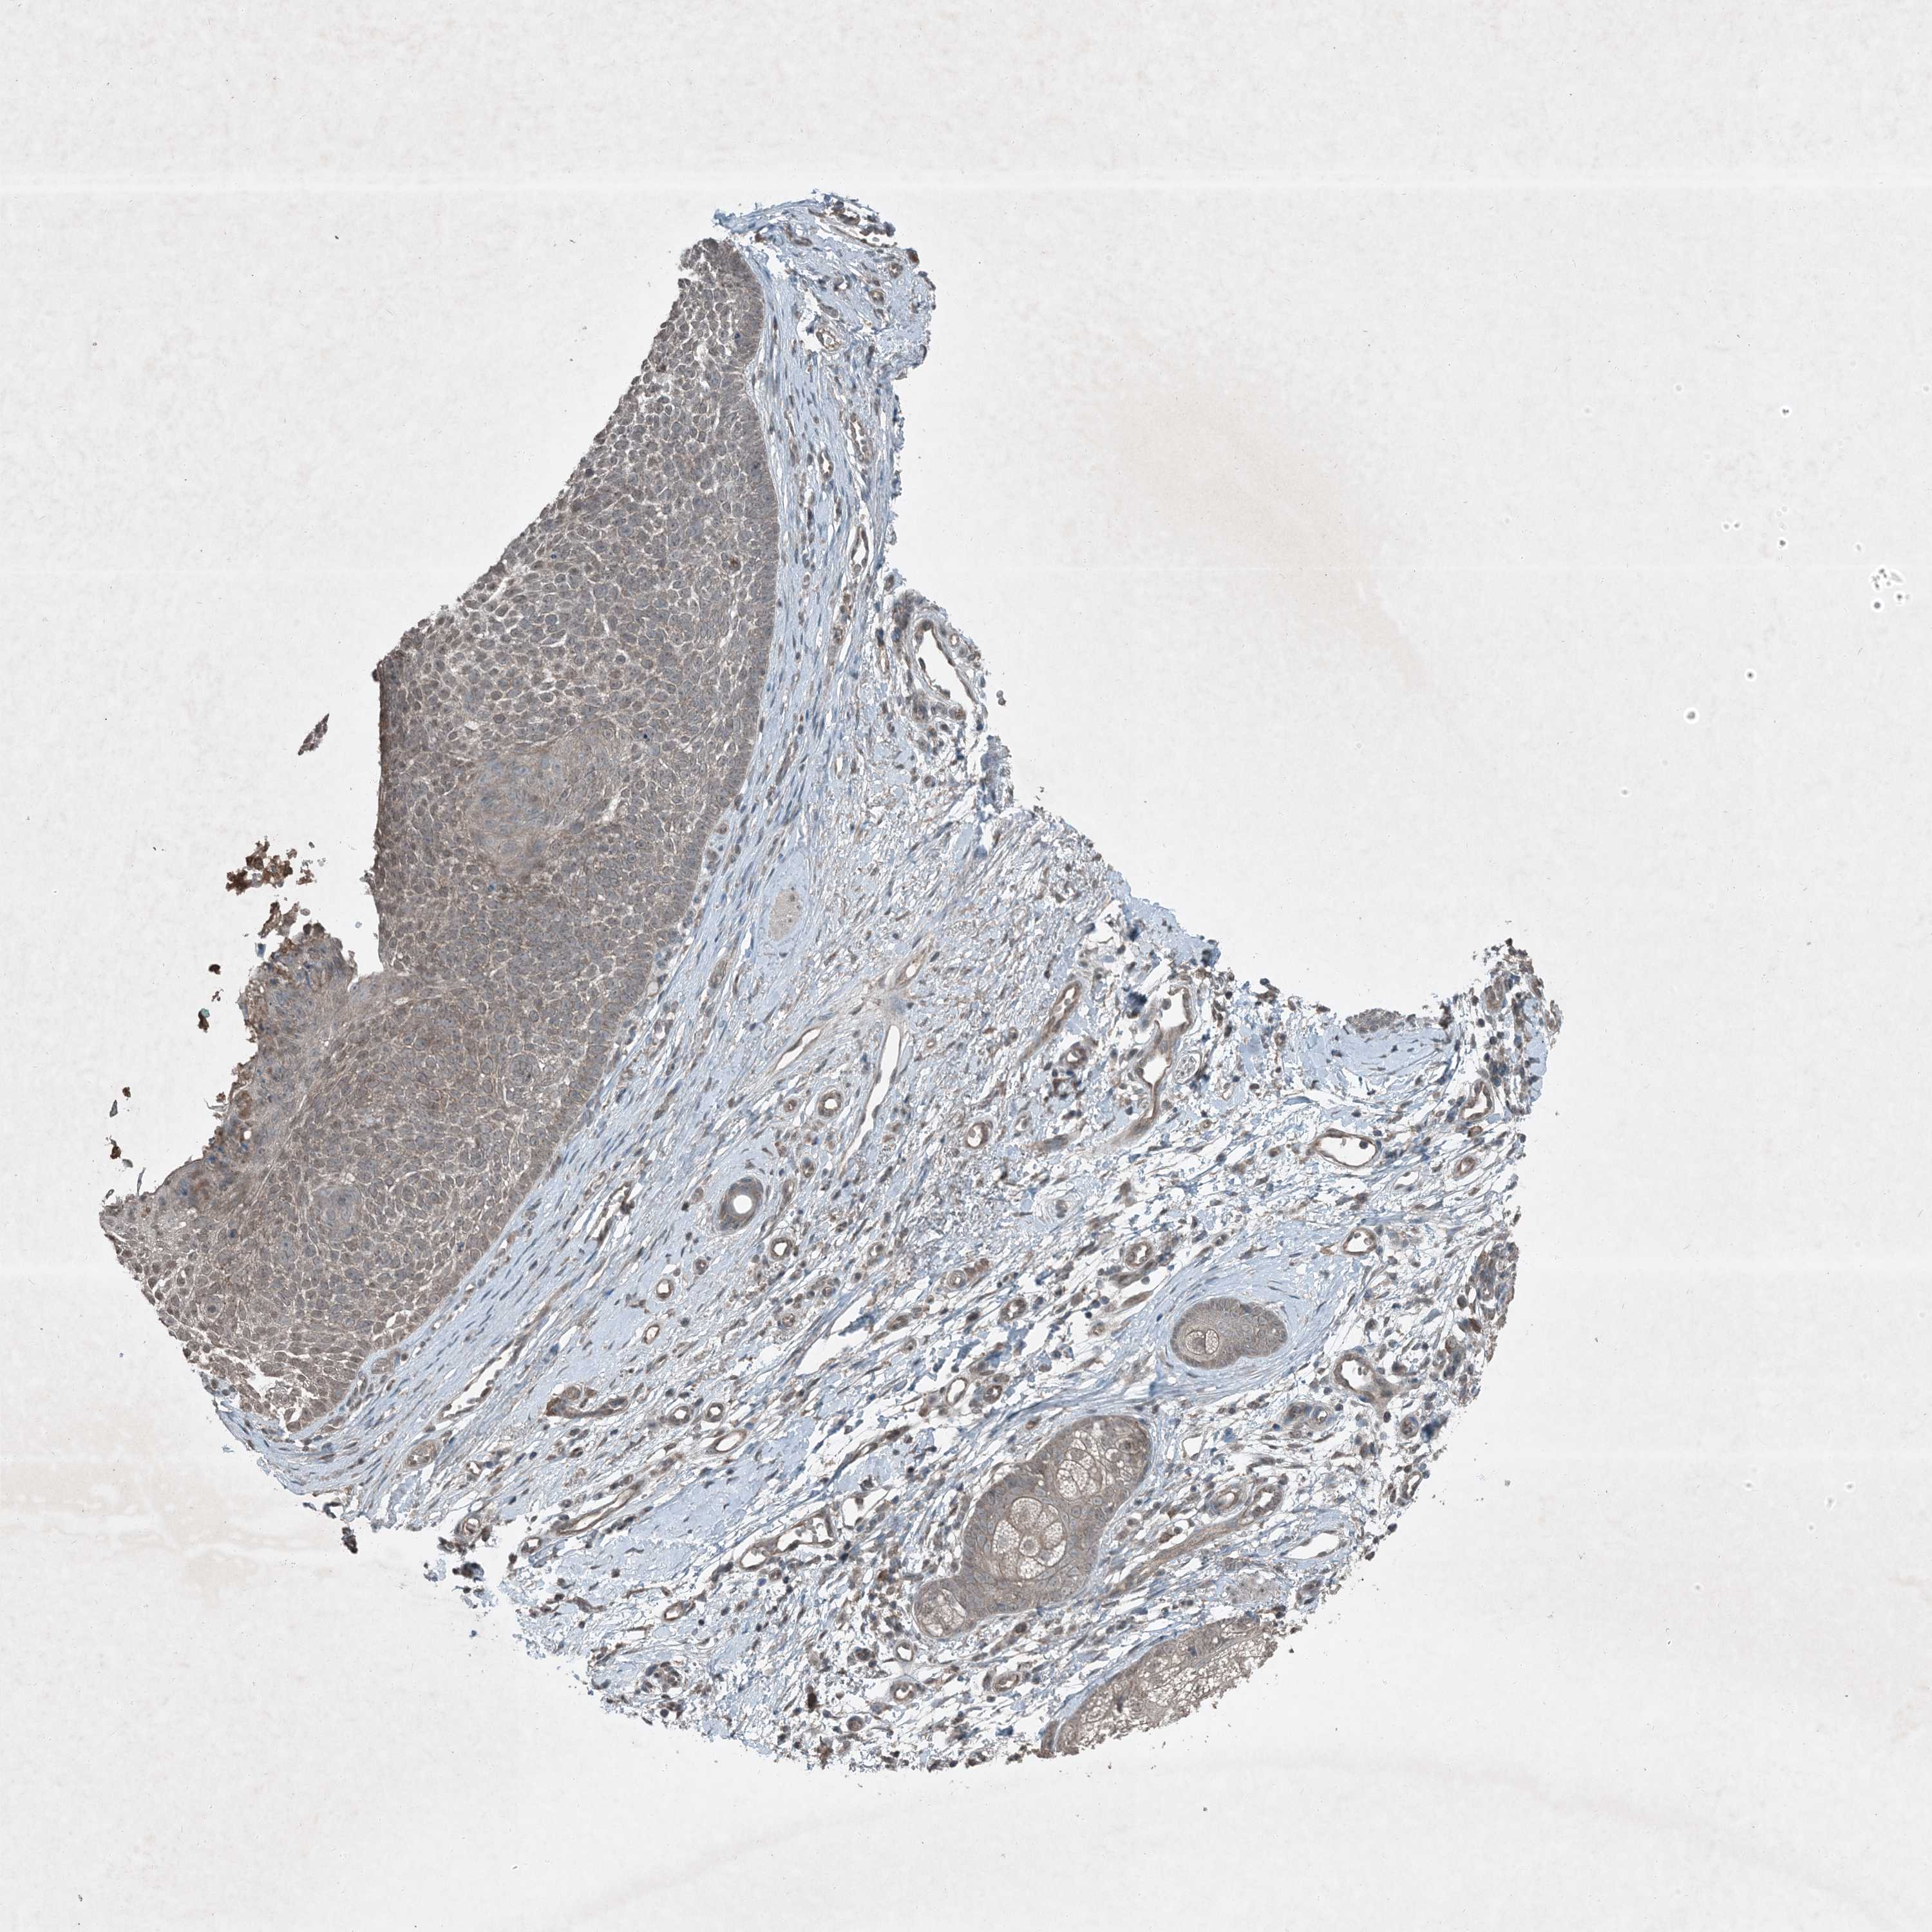

SKIN CANCER - Protein expressioni

A mouse-over function shows sample information and annotation data. Click on an image to view it in a full screen mode. Samples can be filtered based on level of antibody staining by selecting one or several of the following categories: high, medium, low and not detected. The assay and annotation is described here.

Each image is clickable and will lead to virtual microscopy that enables deeper exploration of all samples and also displays staining intensity scores, fraction scores and subcellular localization as well as patient and tissue information for each sample.

Antibody HPA029666

Antibody HPA029667

Antibody HPA029668

Antibody HPA029669

Basal cell carcinoma

Squamous cell carcinoma, NOS

Squamous cell carcinoma, metastatic, NOS